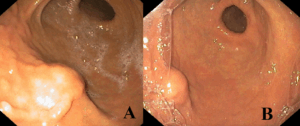

Given these findings, esophagogastroduodenoscopy was performed, revealing a 10-mm subepithelial protrusion along the greater curvature of the stomach, covered by intact mucosa (Figure 1). Mucosal biopsies (bite-on-bite technique) were non-diagnostic.

Figure 1. Upper endoscopy findings. (A, B) Subepithelial bulging along the greater curvature of the stomach, covered by normal mucosa.